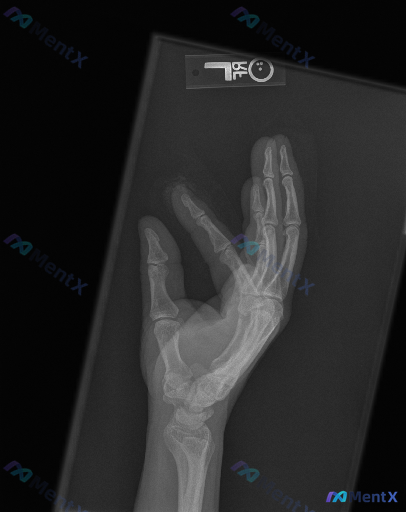

左手斜位X光片:结合临床诉求,影像层面该如何判断?

整理到一份左手斜位X光片的影像分析资料,结合临床有诉求的背景,想和大家讨论下这种情况的判读思路。

影像情况(基于分析报告整理):

- 投照为左手斜位,部分掌骨指骨有重叠,符合该体位表现;

- 可见远端桡尺骨、腕骨、掌骨及指骨,骨皮质连续性良好,骨小梁清晰,未见明确骨折线、皮质台阶或透亮线;

- 各掌指关节、指间关节对位良好,关节间隙未见明显狭窄或增宽,无脱位半脱位;

- 未见明显关节边缘骨质侵蚀、骨赘、软骨下囊性变或硬化,无特异性关节炎征象;

- 未见溶骨/成骨性病灶、骨髓腔密度异常、肌腱韧带钙化或明显副骨/骨骺发育异常;

- 手指软组织轮廓清晰,无明显肿胀、皮下气影或异物影。

临床存在“可能有异常”的诉求,但目前影像层面未发现明确的器质性病变或解剖结构异常。